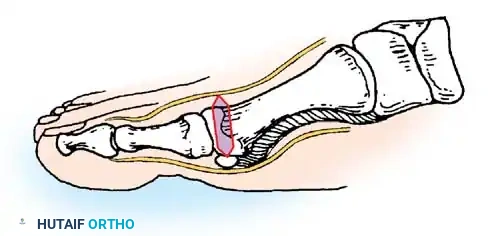

Fig. 78-11 Location of reference points for fi rst and second metatarsals are between 1 and 2 cm from distal articular surface and proximal articular surface of each metatarsal. Because of shorter length of hallux, reference points are placed between 0.5 and 1 cm from proximal and distal articular surface of proximal phalanx. (From Coughlin MJ, Saltzman CL, Nunley JA II: Angular measurements in the evaluation of hallux valgus deformities: a report of the ad hoc committee of the American Orthopaedic Foot and Ankle Society on angular measurements, Foot Ankle Int 23:68, 2002.) support and the medial capsule acting as a spring on stretch. Osteotomy usually is indicated in patients with this medial wedged opening of the joint. If a fi rm forefoot wrap reduces the intermetatarsal angle to a normal value and decreases the hallux valgus angle, however, while congruously rotating the base of the fi rst metatarsal on the medial cuneiform without levering the joint open medially, the McBride procedure can correct the deformity. Correction is improved by excision of the fi bular (lateral) sesamoid because the adductor hallucis and lateral head of the fl exor hallucis brevis are released, markedly reducing the valgus moment at the fi rst metatarsophalangeal joint. In addition, the pull of the fi bular sesamoid on the fl exor hallucis longus through its tendon sheath and pulley system is prevented, reducing another important valgus-producing force on the hallux at the metatarsophalangeal joint. If the fi bular sesamoid is excised, the medial capsule should be repaired with the hallux held in 10 to 15 degrees of valgus. This position must be maintained by a postoperative dressing for 3 or 4 weeks.

AFTERTREATMENT A bulky compression dressing is applied to the forefoot, and the foot is placed in a position of maximal elevation for 48 to 72 hours. Bathroom privileges only are allowed, and the patient must wear a woodensoled shoe. Increased ambulation after 72 hours is allowed as tolerated by the patient. The need for crutches or a walker varies, but assisted ambulation is not encouraged unless the patient is unsteady. At 3 weeks, if the wounds are healed, the sutures are removed, and adhesive strips are applied if needed; leaving the sutures in longer has no untoward effect. Some type of immobilizer or toe spacer to hold the toe in proper alignment is used (Fig. 78-25). The wooden-soled shoe is used for 3 to 4 weeks, at which time a deep shoe with a wide toe box is recommended; a jogging shoe is suffi cient; an extra-depth orthopaedic shoe with a soft toe box also is permissible. The toe spacer is worn for 6 weeks. At 12 to 14 weeks, a reasonably attractive shoe usually can be worn. The period of postoperative edema varies, however, and it may take 4 to 6 months before this type of shoe is tolerated. This is explained to the patient before surgery. DuVries and Mann made major modifi cations in the McBride bunionectomy, including the following:

Weekly postoperative dressing changes for 6 to 8 weeks are emphasized (Fig. 78-26E), followed by use of a night splint that holds the hallux in position until the end of the third month (Fig. 78-27). Mann recommended using the McBride procedure alone in only 10% to 15% of patients undergoing hallux valgus correction. The decision is made intraoperatively by checking reduction of the intermetatarsal angle with manual lateral displacement of the fi rst metatarsal. If the reduction is secure, no proximal metatarsal osteotomy is necessary. In the remaining patients, proximal crescentic fi rst metatarsal osteotomy is done in addition to the distal soft-tissue realignment.